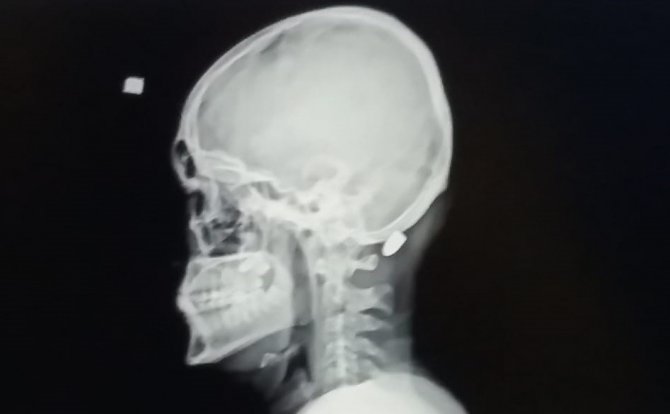

Trabzon'un Vakfıkebir ilçesindeki Karadağ Yaylası'nda bir evin dış cephe kaplamasını yapan 18 yaşındaki Ali Kuleyin'in başına nerden atıldığı belli olmayan kurşun isabet etmiş, ilk önce kurşun olduğunu anlamayan genç, elini başına götürdüğünde kan geldiğini anlayınca hastaneye kaldırılmıştı. İsabet eden yorgun mermi başarılı bir operasyonla saplandığı yerden çıkartılmıştı.